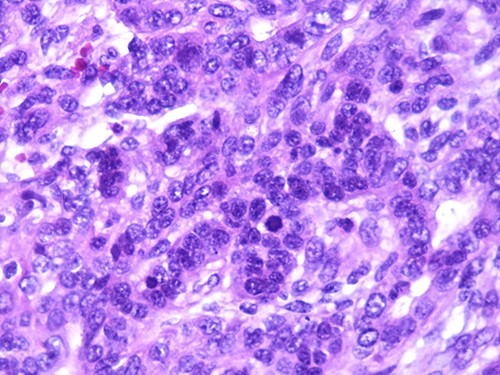

A 46-year-old woman, without clinical antecedent, presented with a tumor in the inner side of the left cheek which had rapidly grown for 3 weeks. Physical examination revealed an ulcerating mass measuring 4 × 3.5 cm, well-circumscribed, fleshly, with a white surface. There was submandibular lymphadenopathy, ranging in dimension from 1 to 1.5 cm in diameter. Magnetic resonance imaging (MRI) scan revealed the tumor of the cheek without mandibular bone infiltration or sinonasal involvement (Fig. 1). Chest computed tomography and abdominal ultrasound scan were unremarkable. An excisional biopsy was performed. Pathological examination showed a neoplastic proliferation composed of mixture of mature benign epithelial components, such as intestinal type, respiratory and squamous epithelia, and mature mesenchymal components, such as muscular tissue and cartilage (Fig. 2) and neuroglial tissue. In addition, immature and malignant tumor components were found such as small blue tumor cells resembling primitive neuroectodermal tumor (Fig. 3), adenocarcinoma and sarcoma with muscular and cartilaginous differentiation (Fig. 4). This tumor infiltrates the skeletal muscle with free margins. Immunohistochemically, epithelial components were positive for pankeratin; mesenchymal components showed desmin, myogenin and S-100 positivity and the primitive neuroectodermal tumor component was positive for NSE, CD99, GFAP, synaptophysin and focally for chromogranin. SALL4 was negative. The resected submandibular lymph nodes were devoid of malignant infiltrate. The diagnosis of TCS was established and the patient was treated by combined chemotherapy (cisplatine +5 fluorouracil) and radiation therapy. No recurrence was noted 6 months after treatment.

Photomicrograph of primitive neuroectodermal component with neural rosettes (magnification at ×400).